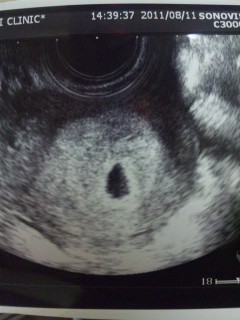

初めて胎嚢確認できたエコーです。7.2mmでした。